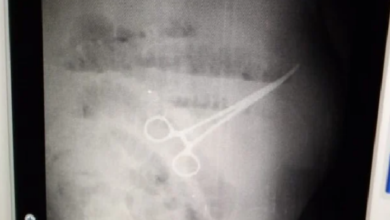

Liberan a dos médicos acusados de dejar tijera en abdomen de paciente

El director de Postgrado de la Universidad del Zulia, Freddy Pachano, informó la liberación de los médicos del Hospital Universitario…